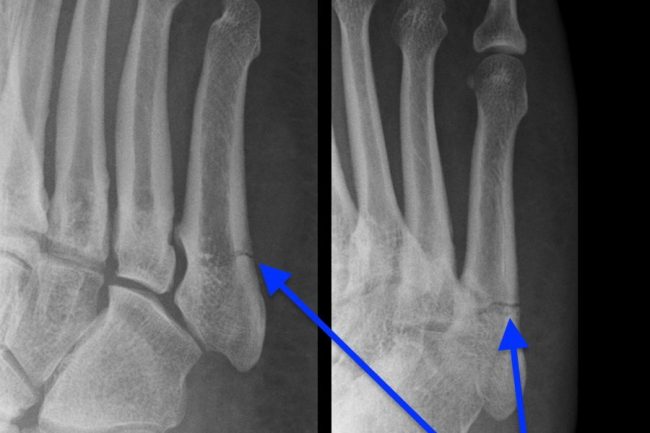

Złamania zmęczeniowe rozbudzają wyobraźnie pacjentów. Bardzo często powodem wizyty u lekarza ortopedy jest właśnie obawa przed tego typu złamaniem, a praktycznie każdy ból kończyny dolnej jest przez pacjentów utożsamiany właśnie z tym problemem. Na szczęście, większość z tych obaw nie znajduje potwierdzenia w rzeczywistości.